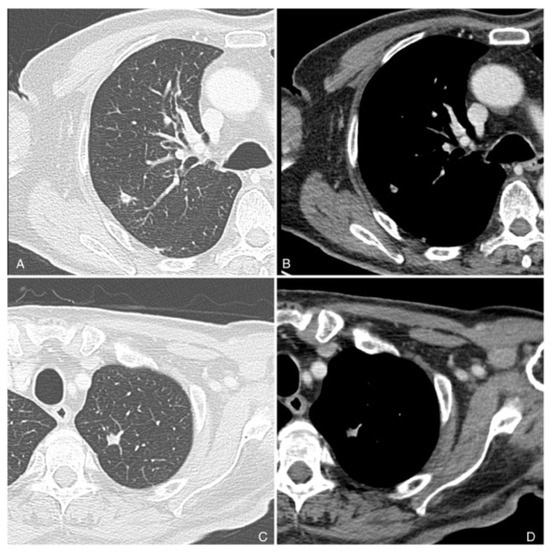

7. The Role of Imaging in Cutaneous Squamous Cell Carcinoma

7.1. CTA Protocol

8. Follow-Up Imaging

- Humphreys, T.R.; Shah, K.; Wysong, A.; Lexa, F.; MacFarlane, D. The role of imaging in the management of patients with nonmelanoma skin cancer: When is imaging necessary? J. Am. Acad. Dermatol. 2017, 76, 591–607, Erratum in J. Am. Acad. Dermatol. 2017, 76, 1226. [Google Scholar] [CrossRef] [PubMed]

- MacFarlane, D.; Shah, K.; Wysong, A.; Wortsman, X.; Humphreys, T.R. The role of imaging in the management of patients with nonmelanoma skin cancer: Diagnostic modalities and applications. J. Am. Acad. Dermatol. 2017, 76, 579–588. [Google Scholar] [CrossRef] [PubMed]